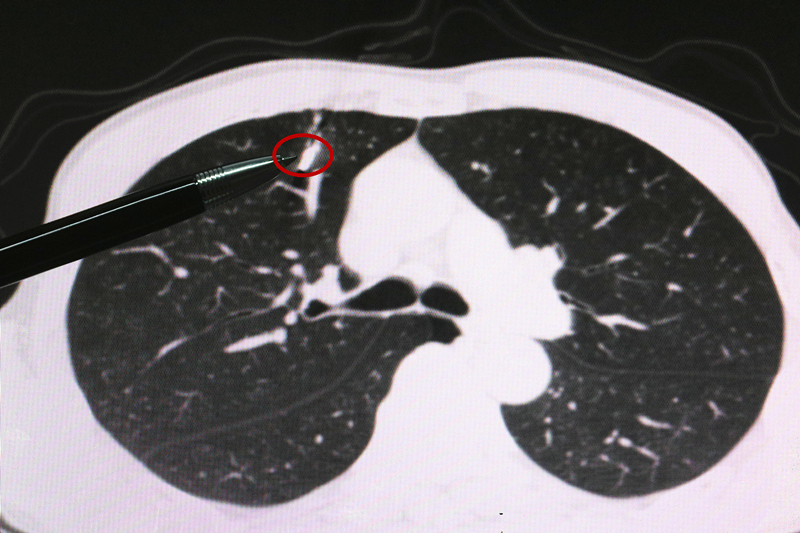

拍完片,做完CT检查以后,接诊的烟台山医院心胸外科主任医师杨军发现:患者右肺上叶有一个长约1.5厘米的异物,胸腔内出现了积血、积气。杨军主任医师结合患者的工作情况断定患者系被锻压产生的金属碎片击伤。

(图中所指为异物,距肺上叶血管仅1毫米)